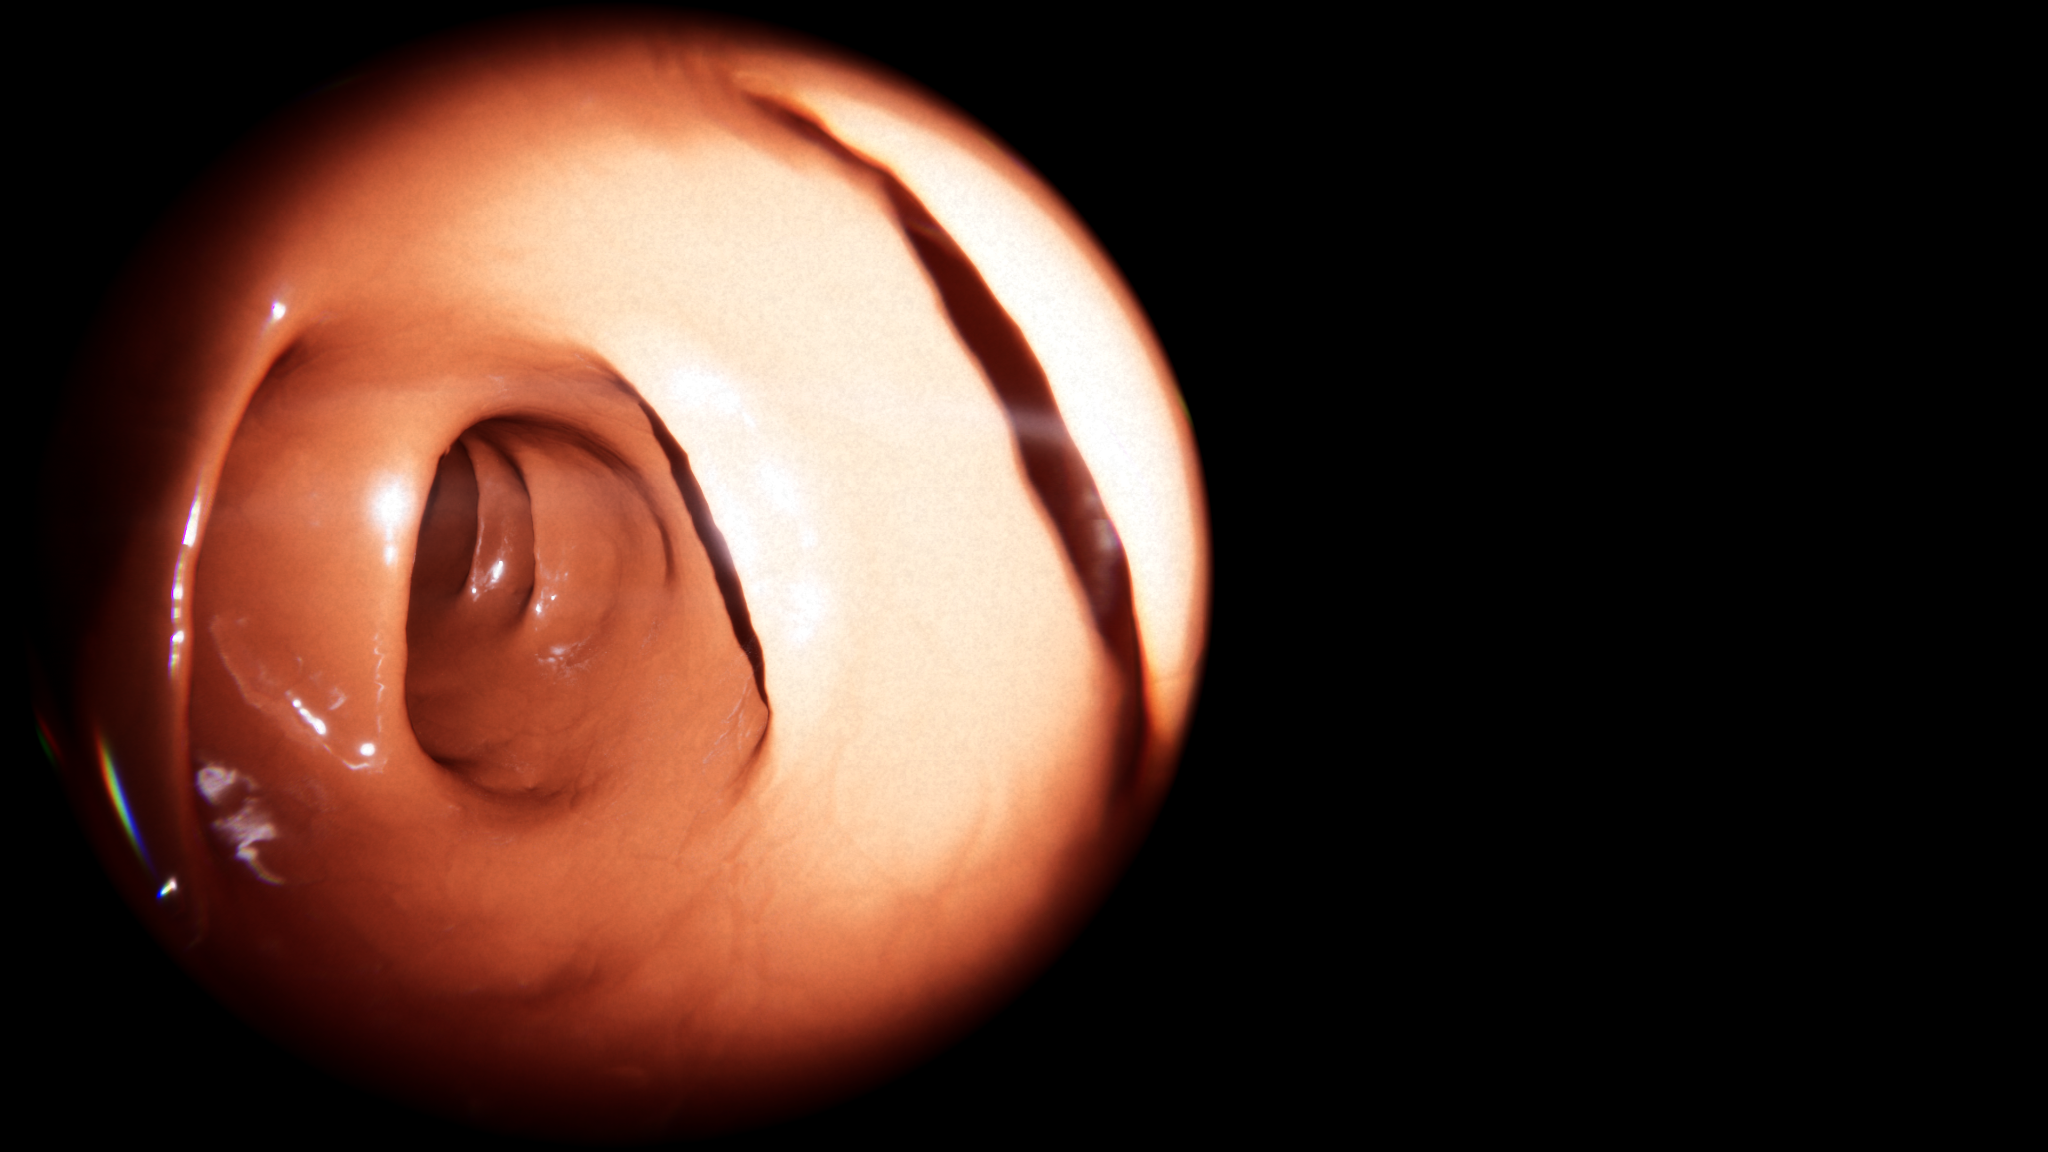

Results showcase that navigating the endoscope through our simulated colon seemingly mirrors real-world operations. Additionally, we use real-patient data to generate the colon model, resulting in a highly realistic virtual colonoscopy simulation. Integrating efficient simulation techniques with practical medical applications arguably advances surgery simulation realism.

One of our main contributions is a simulation pipeline divided into three main parts, starting with the acquisition and reconstruction of the colon from a real patient CT (a). Then, the colon centerline is extracted and used to build a spline skeleton (b), which will be used to model the colon and the endoscope. The physical deformation is produced using an XPBD formulation and a tailored collision detection method during the simulation (c).